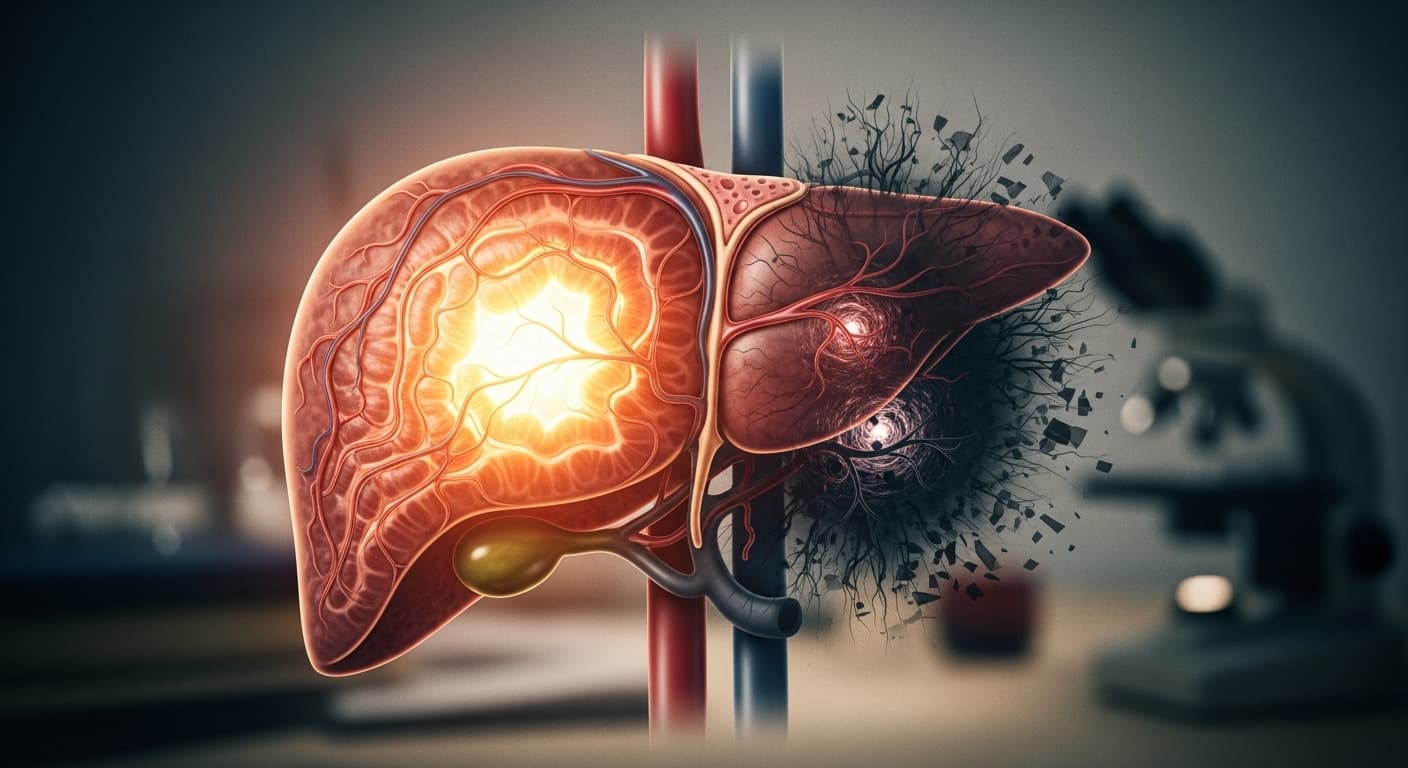

따스한 햇살과 함께 새싹이 돋아나는 봄은 참 아름답지만, 혹시 요즘 눈이 뻑뻑하고 침침하거나, 작은 일에도 쉽게 짜증이 나지는 않으신가요? 봄은 만물이 소생하는 계절인 동시에, 우리 몸의 간(肝)이 가장 활발하게 활동하며 또 쉽게 지치기도 하는 시기랍니다.

한방에서는 간이 '피로와 감정'을 다스리는 중요한 장기로 보고 있어요. 특히 눈은 '간의 창문'이라고 불릴 만큼 간 건강과 밀접하게 연결되어 있죠. 봄철의 춘곤증이나 미세먼지 등으로 눈 피로가 가중되면 간에도 무리가 가고, 이는 곧 짜증이나 불안감 같은 감정적인 변화로 이어지기 쉽습니다.

첫 번째 포스트, '만성 스트레스? 당신의 간(肝)이 화내고 있다!' 에서는 일상 속 스트레스가 우리 간에 어떤 영향을 미치고, 그것이 어떻게 짜증이나 두통 같은 증상으로 나타나는지 깊이 있게 다뤄보았어요. 혹시 내 간도 지금 화를 내고 있는 건 아닌지 한번 살펴보는 시간이 되실 거예요.

두 번째 포스트인 '스마트폰 달고 사는 당신! 디지털 눈 피로, 간 때문이야?' 는 현대인의 고질병인 스마트폰 사용으로 인한 눈 피로가 단순한 눈 문제가 아닌, 간 건강과 어떻게 연결되어 있는지를 명쾌하게 설명해 준답니다. 눈 건강 관리가 곧 간 건강 관리라는 사실에 깜짝 놀라실 수도 있어요.